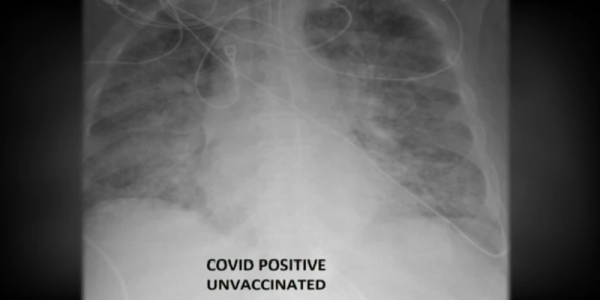

Ренгденски снимки на белите дробови на вакцинирано и невакцинирано лице, и двајцата заразени со САРС-КоВ-2, ја покажуваат разликата за тоа како вирусот делува откако целосно ќе се имунизирате. Доктор Гасан Камел од Универзитетската болница во Сент Луис, кој раководи со одделот за интензивна нега, вели дека сака да го насочи вниманието на важноста на вакцинацијата, која спречува тешки форми на болеста.

Белите дробови треба да бидат полни со воздух, а воздухот на рендгенските снимки изгледа црно. Ако погледнете, ќе видите дека снимката на невакцинираниот пациент е матна, повеќе бела отколку црна. Тоа значи дека пациентот мора да е на кислород, а можеби и повеќе од тоа, можеби мора да е на вештачка вентилација, респиратор и други системи за одржување на виталните функции на вештачки начин, вели тој.

Белите дробови на ковид-позитивен пациент кој не бил вакциниран

Пациентите кои се вакцинирани можеби нема да ја видат ни внатрешноста на собите во болница. Не им е потребна интензивна нега и не им е потребен респиратор, додава тој.